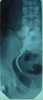

May Cause

Urinary tract gas